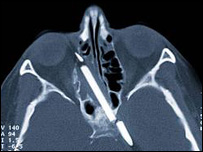

पचपन वर्षों से सिर में फंसी पेंसिल हटाई गई | |||||||||||||||||||||||||||||||||||||||||||||||||||||||||||||||||||||||||||||||||||||||||||||

जीवन के 55 साल सिर में फंसी पेंसिल के साथ गुज़ारने के बाद जर्मनी की इस महिला को आख़िरकार इससे होने वाले कष्टों से मुक्ति मिल ही गई. मार्ग्रेस वेगनर तब चार साल की थी, जब वह एक हादसे के दौरान गिर गई थी और पेंसिल उनके गाल में घुस गई थी. इस पेंसिल का कुछ हिस्सा दाहिनी आँख के कुछ ऊपर मस्तिष्क तक धंस गया था. 59 वर्षीय वेगनर को इसके कारण अक्सर सिरदर्द और नाक से खून बहने की शिकायत रहती थी. मुश्किल ऑपरेशन बर्लिन में सर्जनों ने लगभग दो घंटे के ऑपरेशन के बाद पेंसिल को मस्तिष्क से हटा दिया. लेकिन अब भी क़रीब दो सेंटीमीटर लंबा पेंसिल का टुकड़ा वेगनर के मस्तिष्क में फंसा हुआ है और डॉक्टरों का कहना है कि इसे हटाना नामुमकिन है. इस मुश्किल ऑपरेशन को अंजाम देने वाले इंडोस्कोपिक सांइस सर्जरी के विशेषज्ञ प्रोफ़ेसर हेंस बेरबोहम ने कहा कि वेगनर अब चल-फिर सकती हैं और उन्हें किसी तरह का दर्द नहीं हो रहा है. बेरबोहम ने बीबीसी से कहा, "पेंसिल के बीच का हिस्सा कोमल तंतुओं से ढका है और इससे मरीज़ को किसी तरह का ख़तरा नहीं है." उन्होंने कहा, "ऑपरेशन के लिहाज़ से ये हिस्सा बेहद संवेदनशील है. आधुनिक मेडिकल तकनीक से इसे हटाने में भी कुछ जोखिम है." उन्होंने कहा, "वेगनर को अब सिरदर्द की शिकायत नहीं है और वह अपने आसपास की गंध को सूंघ सकती हैं." मस्तिष्क में फंसी इस पेंसिल की लंबाई कोई आठ सेंटीमीटर थी और आँख का संवेदनशील हिस्सा इससे होने वाले नुक़सान से बाल-बाल बचा था. हादसे के वक़्त डॉक्टरों का कहना था कि अभी ऑपरेशन करना बेहद ख़तरनाक़ है, क्योंकि पेंसिल मस्तिष्क के काफ़ी क़रीब थी. | इससे जुड़ी ख़बरें सिगरेट पीने से दिमाग पर गहरा असर25 फ़रवरी, 2007 | विज्ञान नींद पूरी ना होय तो...10 फ़रवरी, 2007 | विज्ञान दिमाग़ी चोट में फ़ायदेमंद है शराब24 दिसंबर, 2006 | विज्ञान मस्तिष्क की बीमारियों के लिए उम्मीद15 दिसंबर, 2006 | विज्ञान झूठों का सफ़ेदी से ताल्लुक!30 सितंबर, 2005 | विज्ञान दर्द घटाती है, दर्द कम होने की सोच06 सितंबर, 2005 | विज्ञान जम्हाई का मतलब है जागने की कोशिश04 जुलाई, 2007 | विज्ञान | |||||||||||||||||||||||||||||||||||||||||||||||||||||||||||||||||||||||||||||||||||||||||||||